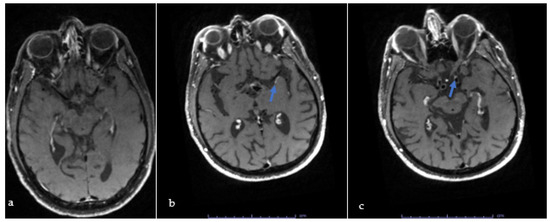

Diagnostic Yield of High-Resolution Vessel Wall Magnetic Resonance Imaging in the Evaluation of Young Stroke Patients

(1) Background: The mechanism responsible for stroke in patients younger than 50 often remains unknown. This study was designed to assess whether high-resolution intracranial vessel wall MR imaging (icVWI) may be instrumental in determining stroke cause. (2) Methods: Young stroke patients with and [...] Read more.

(1) Background: The mechanism responsible for stroke in patients younger than 50 often remains unknown. This study was designed to assess whether high-resolution intracranial vessel wall MR imaging (icVWI) may be instrumental in determining stroke cause. (2) Methods: Young stroke patients with and without an identified cause of stroke despite an exhaustive investigation were prospectively included. Patients who underwent icVWI were compared to those who did not. We next compared patients with and without intracranial vulnerable plaques on icVWI. (3) Results: Overall, 47 young stroke patients were identified over the span of 2 years and included in this study. Of those, 20 (42%) underwent intracranial icVWI. Cancer prevalence was higher among patients who did not have an icVWI study (19% vs. 0% p = 0.042) but there were no other significant differences between patients who had an icVWI study and those who did not have an icVWI. Among patients who had an icVWI, 11 (55%) had vulnerable plaques and the remaining nine studies were negative. Patients with positive icVWI scans had significantly higher stroke severity at admission (mean ± SD NIHSS score 5.5 ± 3.5 vs. 1.7 ± 2.3, p = 0.012). Patients with positive icVWI scans were more often treated with antiplatelets upon discharge (100% vs. 67%, p = 0.038). (4) Conclusions: icVWI can add significant information relevant to stroke pathogenesis and secondary prevention among young stroke patients with a negative exhaustive diagnostic workup. Full article